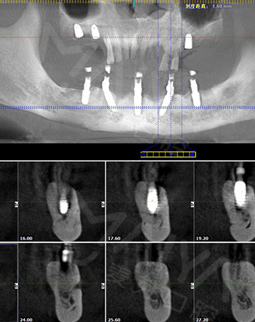

麦芽的博士专家团在看过我的片子后发现,我的牙齿由于长期对口腔疏于护理,牙周情况非常差,余牙有些松动,且牙槽骨萎缩严重,现存的骨量无法进行传统的种植牙手术,因此给我设计了“all-on-4”种牙技术的升级版本“all-on-5”,前期是要处理我的牙周问题,当天就给安排了洁牙,然后上药,等牙周恢复差不多就可以进行种植了!

经过一个月的牙周治疗,牙齿肿胀部分都已经消退,来麦芽种牙之前,心理还有点小紧张,总害怕种牙特别疼,恢复时间慢。我的牙齿情况比较复杂,部分牙齿有牙槽骨吸收,经过前期的各种检查,医生说我的身体状况适合种牙。